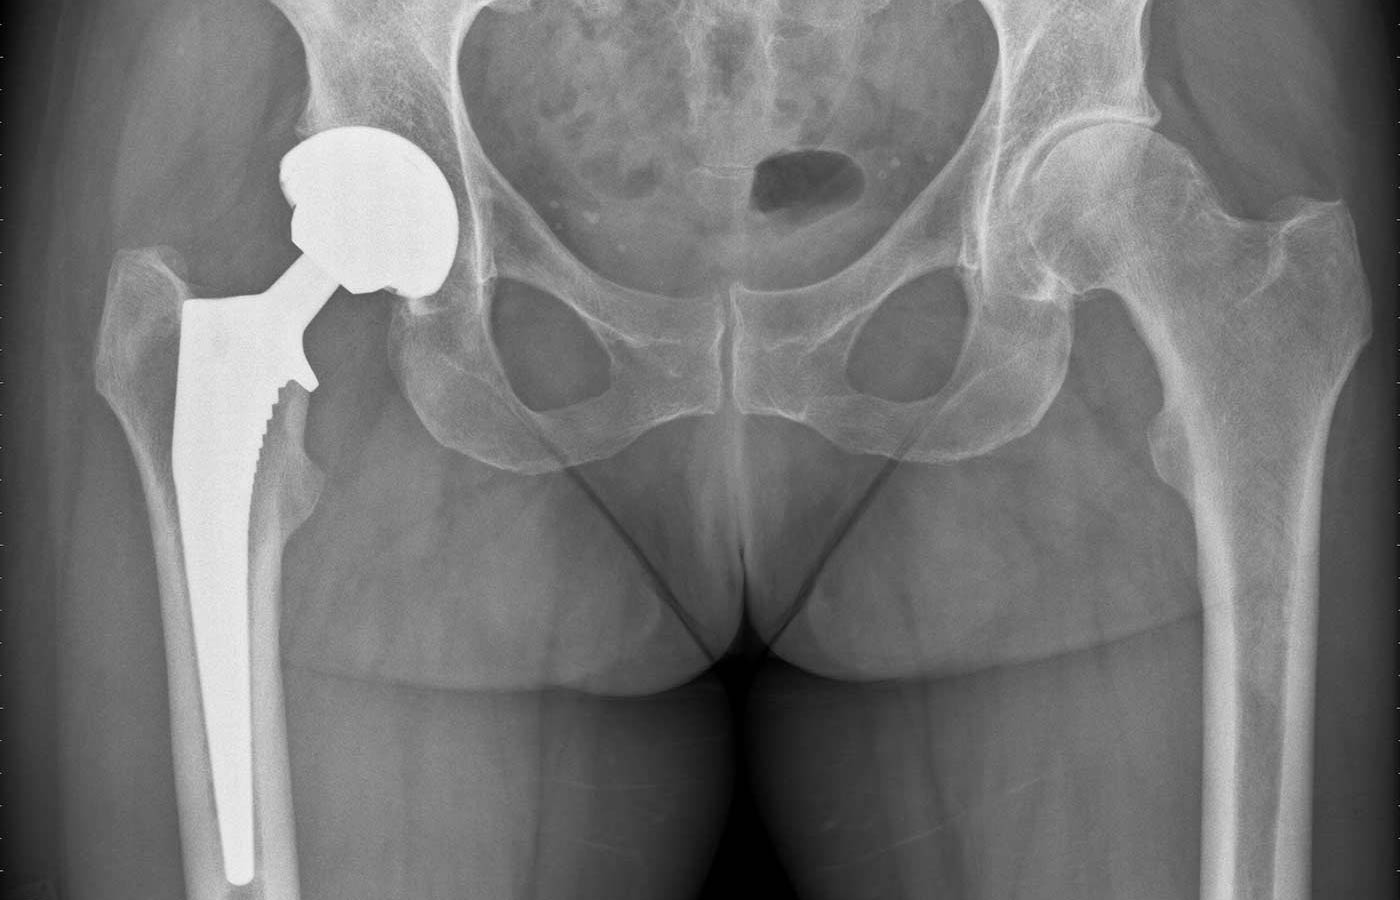

Nach der Implantation einer zementfreien Hüftprothese